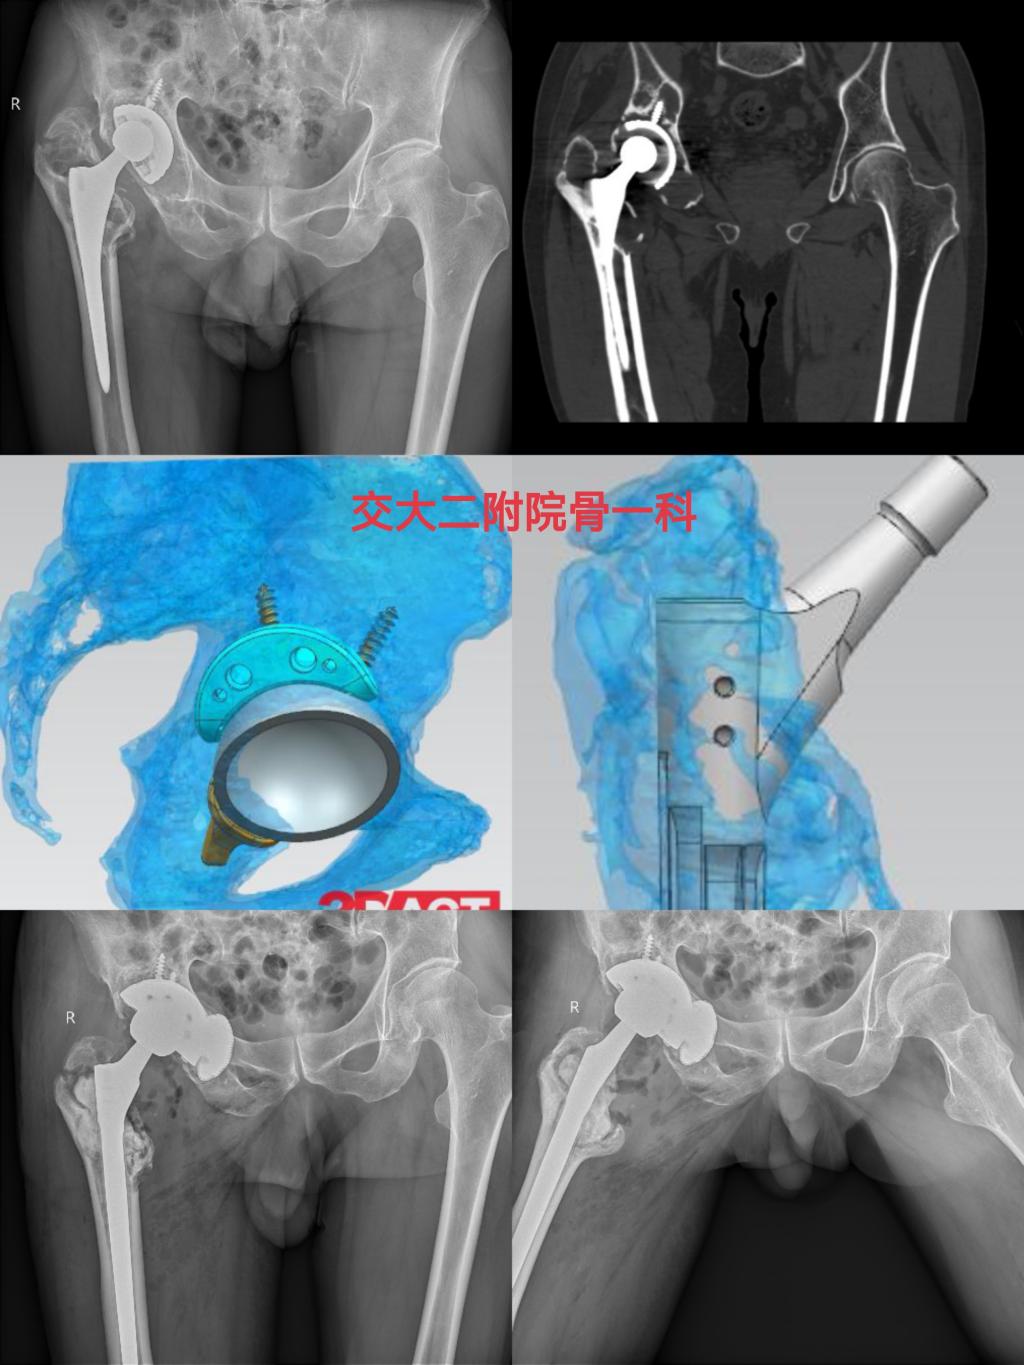

近期,一位左髋关节置换术后10余年、疼痛伴跛行2年的老年患者求助于骨一科,入院诊断为左髋关节置换术后假体松动,髋臼骨缺损(PaproskyⅢa型),股骨骨缺损(Paprosky Ⅱ型),骨质疏松症,完善相关检查排除手术禁忌后,由党晓谦主任主刀完成左髋关节假体翻修手术,术后恢复良好,已顺利出院。